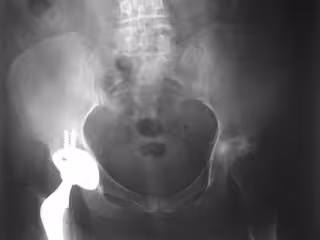

Reemplazo de cadera